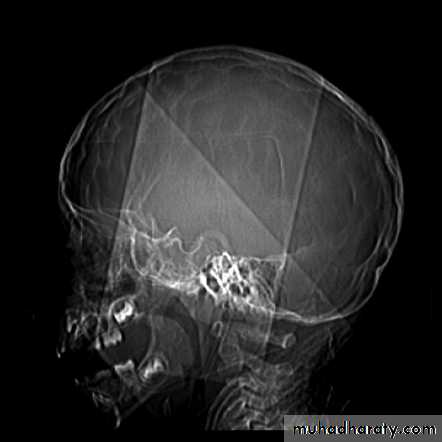

Skull X-ray findings in increased intracranial pressure

• Sutural separation in children.

• ‘Copper-beating’ marking of the cranial vault.

• Thinning of dorsum sellae.

• Erosion of the posterior clinoid process.

Copper-beating’ marking